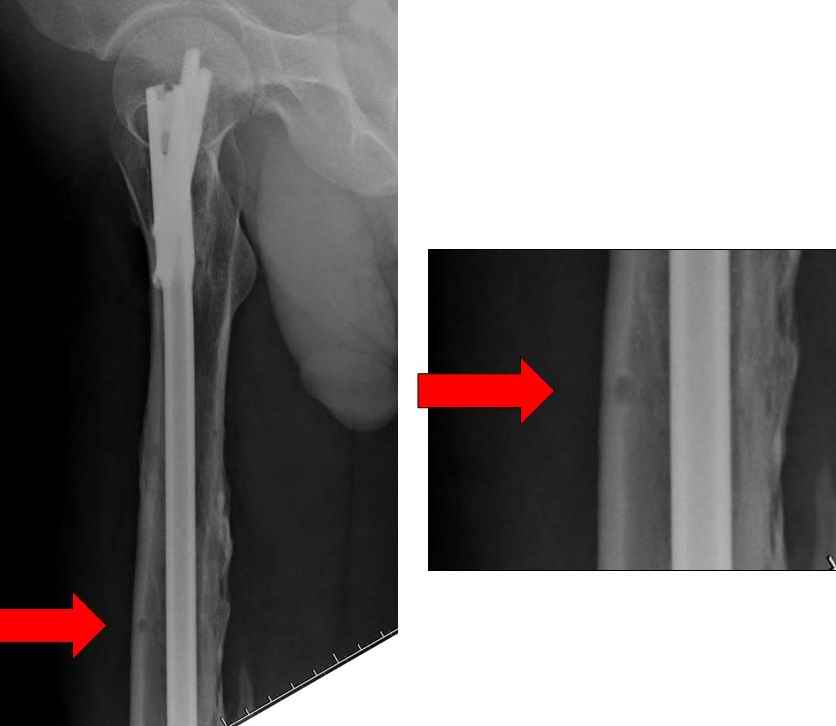

Инфекция канала и стрессовый перелом:

Представляю снимки больного с политравмой: леченного в другом мед.учреждении по поводу открытого перелома бедра, сперва аппаратом наружной фиксации, затем пластиной. Обратился к нам через 8 месяцев после удаления пластины с проблемой несросщего перелома бедренной кости, без клинических проявлении к инфицированию (не все снимки сохранены)

Рутинный интрамедуллярный остеосинтез с расверливанием и с фиксацией реконструктивным трокантерик штифтом (рис №1, №2),

если первые 4 месяца послеоперационного периода проходил без проблем, но на 5 месяце появились боли в дистальном отделе бедра и температура, т.е. симптомы медуллярного инфицирования (рис №3, №4).

При обзоре причин перелома, на снимке №2 обнаружили, что один из стержней аппарата наружной фиксации проходил только через передний кортекальный слой, что создало стрессовую зону на бедре и в результате перелом из-за незначительной травмы.

На снимке N2 виден канал от стержня во фронтальной плоскости, на уровне которого на снимке N7 уже перелом.